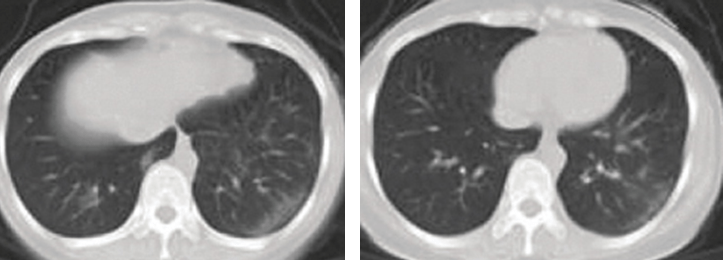

Chest computed tomography (CT) scan showed multiple ground glass appearance in both lungs. She was diagnosed with pneumonia and admitted to hospital. During her stay on a general medical ward, she was prescribed the antibiotic ceftazidime and a patent Chinese herb infusion (Xiyan Ping) for 4 days but showed no significant improvement.

• A third CT scan showed almost complete disappearance of the ground glass appearance. On discharge the patient had complete resolution of symptoms.